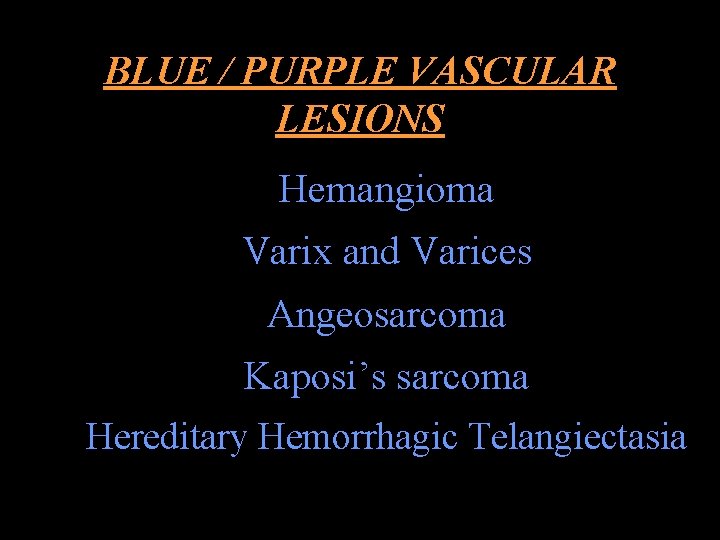

BLUE / PURPLE VASCULAR LESIONS Hemangioma Varix and Varices Angeosarcoma Kaposi’s sarcoma Hereditary Hemorrhagic Telangiectasia